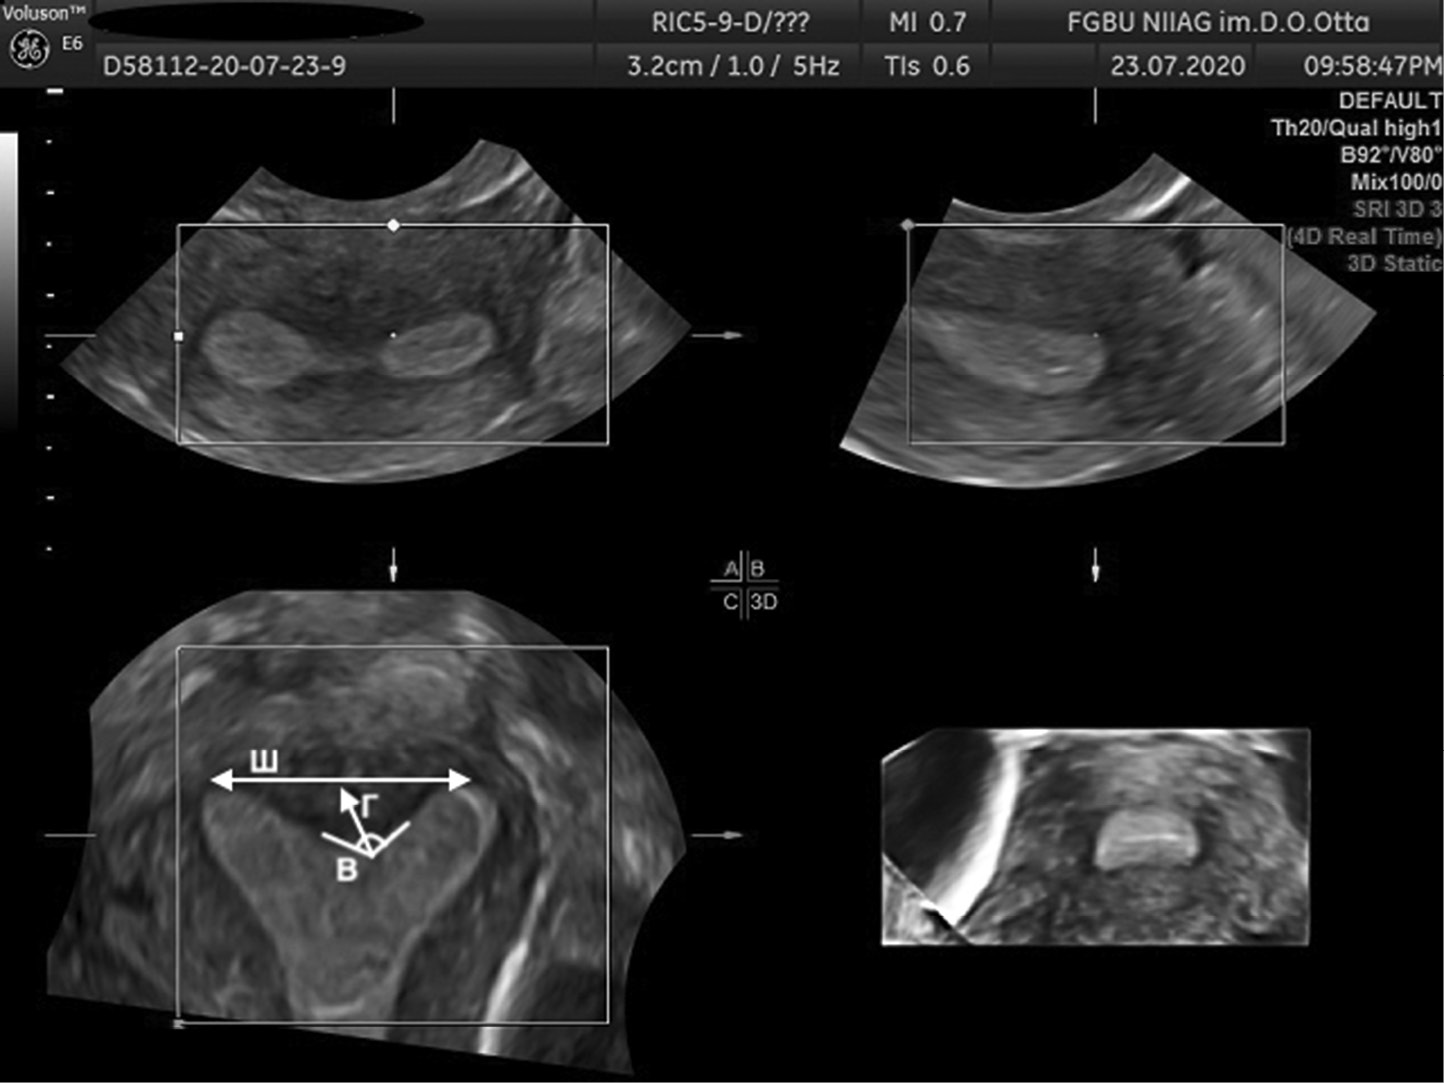

The AFS proposed to assess parameters, such as Г, cavity indentation; Ш, uterine cavity width; and B, angle of cavity indentation (Figs. 1–4).

Fig. 4. 3D ultrasound reconstruction of the uterine cavity: normal uterus, where Ш, uterine cavity width; Г, cavity indentation; B, angle of cavity indentation

Рис. 4. Ультразвуковая 3D-реконструкция полости матки — нормальная анатомия матки: Ш — ширина полости матки; Г — глубина вдавления полости матки; угол В — угол вдавления полости

Uterine septum is diagnosed using the following indicators: Г ≥15 mm, angle B <90º, while uterus arcuate is diagnosed using the following indicators: D ≥10 mm, but <15 mm and angle B >90° [11].